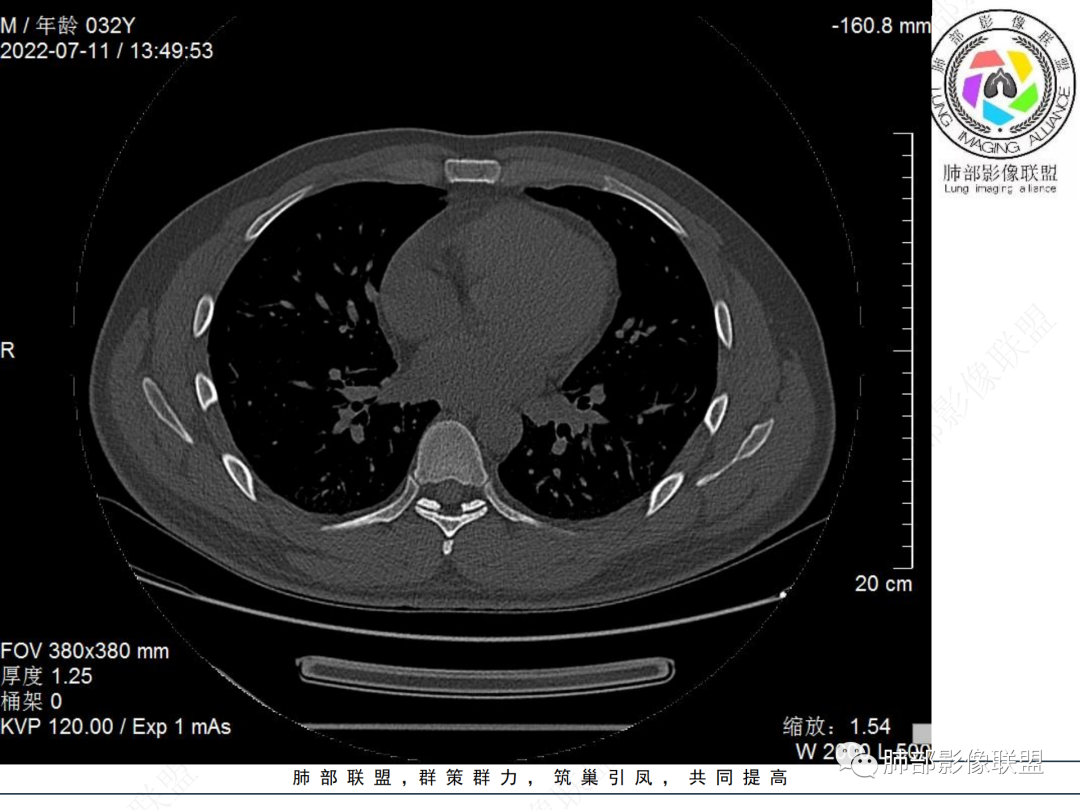

左肺下叶后基底段开口处结节,边缘光滑清楚,没有增强扫描,年轻男性患者痰血三天,考虑1.良性病变:腺瘤、错构瘤、平滑肌瘤

2.恶性:类癌、粘液表皮样癌。

左肺下叶外后基底段气管内见结节状影,边缘部分清晰。考虑错构瘤,待排恶性病变。

左肺下叶气管内外占位病变,咯血病史,考虑类癌,粘表待排。

青年男性,左肺下叶后基底段支气管开口软组织结节,边缘光整,气管镜提示质软,易出血,考虑类癌

左肺下叶后基底段开口处腔内见壁结节,花生米样,宽基底,补充增强及矢状位重建,确定我无向壁外突破浸润生长,另见强化的特点,临床触之易出血,类Ca可能性大。

年轻男性,咳血,左肺下叶后基底段支气管腔内结节,边缘光滑,首先考虑青年三件套,类癌大于粘液表皮样癌,支气管镜质软,触之易出血,鉴别血管瘤,平滑肌瘤

左肺下叶后基底段开口部结节,密度较均匀一致,边缘较光整,目测密度偏低,支气管镜示:质软、触之易出血,考虑恶性,类癌。

左肺下叶后基底段支气管腔内结节,有蒂,容易出血,先考虑良性病变,肉芽组织型血管瘤,与类癌鉴别。